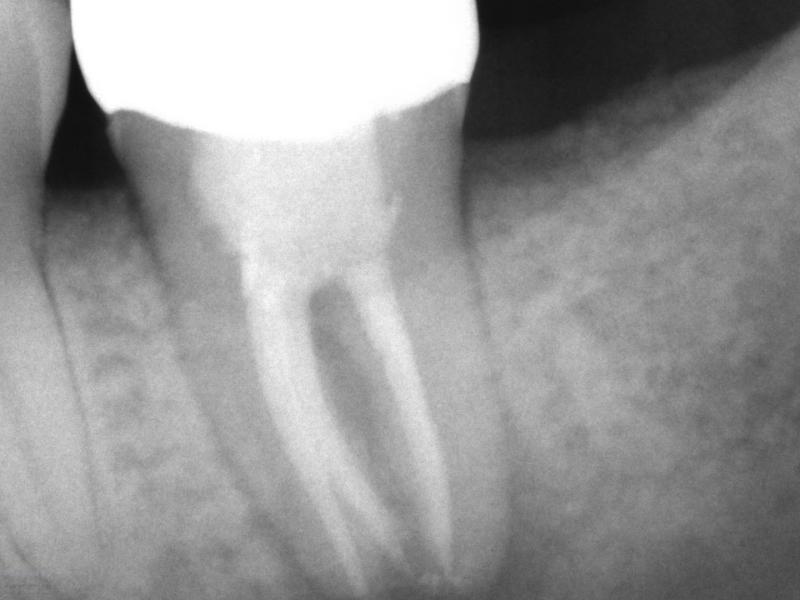

Recall